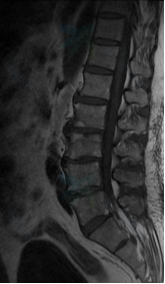

入院后给予逐级止痛治疗,但症状无明显缓解;为更加详细明确病因及病变位置,拟行腰椎MRI、左髋关节MRI及全身骨扫描等相关检查,但患者因剧烈疼痛无法平躺配合,为解决这一难题,遂邀请我院麻醉科会诊,在麻醉科谭敬老师、袁伟老师、宋珂珂老师的积极努力下,成功完成硬膜外麻醉并置管,患者疼痛症状明显缓解,使得检查顺利进行,结果显示:MRI检查示腰2/3椎体信号异常,再结合抽血检验示结核杆菌T细胞检测阳性这一指标,遂考虑病变部位可能为腰2/3结核感染可能。为进一步明确病变责任部位,于局麻下为该患者行腰3神经根封闭术,封闭后病人症状明显缓解,证实了先前诊断。杨益民副主任医师与患者及家属充分沟通后,决定采用微创椎间孔镜手术方式给予患者行结核病灶清除、神经根探查松解术,手术过程顺利,术后病人症状完全缓解,病人及家属对我院诊疗水平表示十分满意。

腰椎MRI示:腰2、3椎体信号异常,椎管内异常信号影